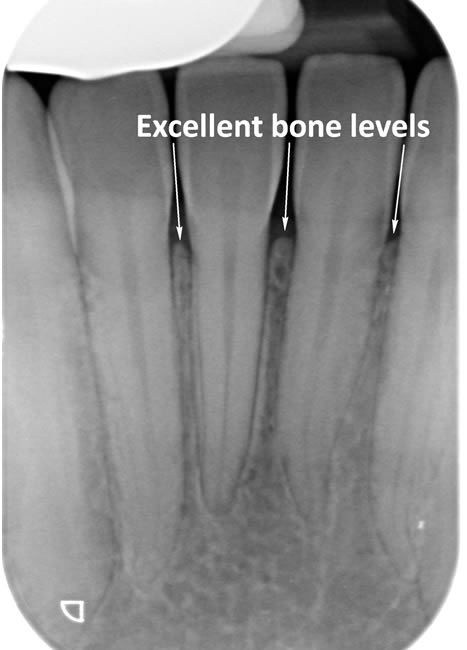

The diagrams below show the different stages of gum disease

Periodontitis is a more advanced stage of gum disease where there has been damage to the bone which supports the teeth. If left untreated periodontitis leads to more and more bone loss until the teeth start to become loose and eventually fall out by themselves or need to be extracted by a Dentist.

The main cause of gum disease is plaque. Plaque consists of millions of bacteria which live on and around the teeth and gums. These bacteria produce toxins which damage the gums. To begin with the gums start to peel away from the teeth and “pockets” form. As the bacteria penetrate deeper into these “pockets” they then start to cause damage to the bone which holds the teeth in. As more bone loss occurs the teeth start to become increasingly looser until they eventually start to fall out one by one.